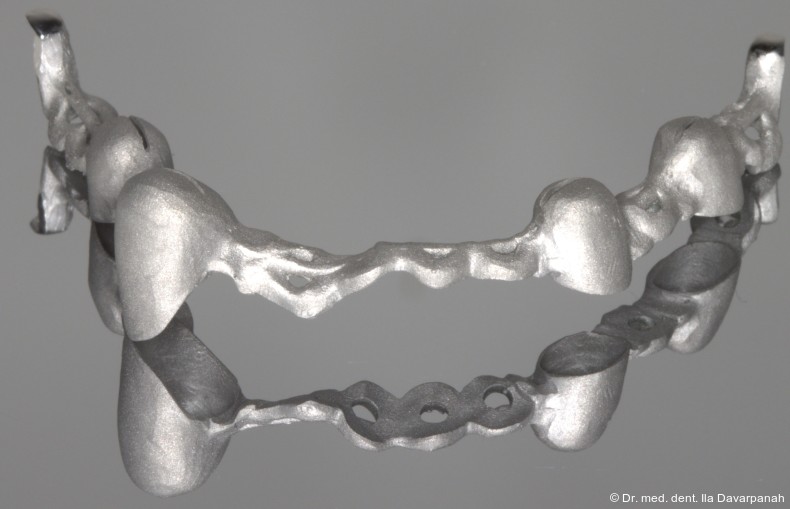

Der Gesamtaufbau des Halteelementes besteht aus einer konischen Zirkonoxid-Patrize (Primärteil) und einer galvanisch hergestellten Sekundärkappe. Das Tertiärgerüst wird aus einem Nichtedelmetall (NEM) mittels Selective Laser-Melting (SLM) gefertigt, was eine hohe Passgenauigkeit und ein günstiges Kosten-Nutzen-Verhältnis ermöglicht. Werkstoffe wie Titan, Acetal oder Polyetheretherketon (PEEK) sind nicht für die Herstellung des Tertiärgerüstes geeignet, da sie eine hohe Eigenbeweglichkeit mitbringen.

Auf Basis des digitalen Mock-ups wurden die Zirkonoxid-Primärkappen, galvanisch hergestellten Sekundärkappen sowie das NEM-Tertiärgerüst laborseitig gefertigt (Abb. 13+14). Die intraorale Verklebung der Sekundärkappen mit dem Tertiärgerüst erfolgte spannungsfrei im Mund (Abb. 15–17).